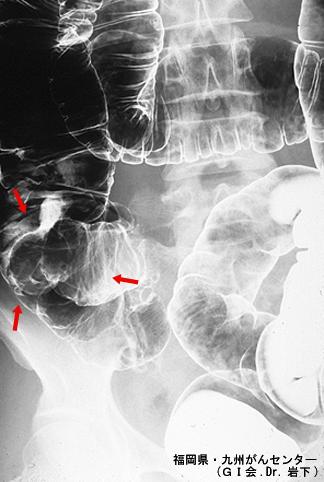

症例提示(所在地,施設名等): 福岡県・ 九州がんセンター (Dr.岩下)

疾患(病理主体)の分類腫瘍様病変/炎症性類線維ポリープ(IFP)

部位(臓器別)大腸/回盲部

検査方法X-P

病変の最大径(ミリ)30〜34